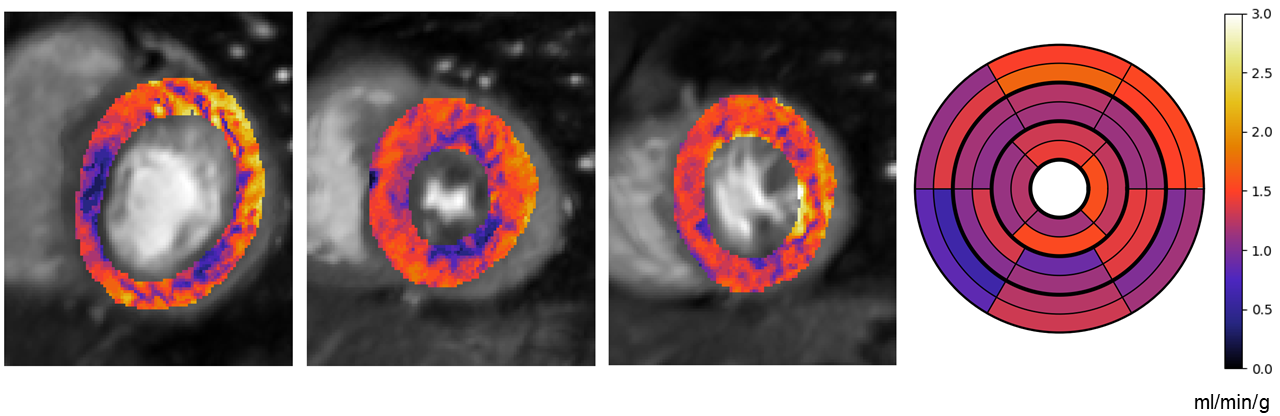

A training set of matched data and labels is required to find the best set of model parameters to map the input data to labels. The trained models can subsequently be applied to unseen test data to obtain a prediction of its label. This is opposed to unsupervised learning which attempts to learn structure in the data Goodfellow2016.

Deep learning

Deep learning is the sub-field of machine learning based primarily on the use of neural networks Goodfellow2016. Artificial neural networks are functions made up of layers of units or neurons. Each unit in a layer takes, as input, the output of the units in the previous layer. It then computes a weighted combination of these inputs and applies a non-linear activation function. The weights needed for the weighted combination are the parameters of the neural network and are optimised in order to solve the task at hand. The typical neural networks composes many internal layers and are thus described as deep. A simple neural network, with two hidden layers (layers in addition to the input and output layers), is illustrated in Figure 5.2 As previously discussed, the early layers can be thought of as extracting features from the input data, while the later layers learn to combine these features to meet the objective. This yields a model function in the form:

f𝜽(x)=f𝜽𝑳L(f𝜽𝑳𝟏L1(f𝜽𝟎0(x)))subscript𝑓𝜽𝑥subscriptsuperscript𝑓𝐿subscript𝜽𝑳subscriptsuperscript𝑓𝐿1subscript𝜽𝑳1subscriptsuperscript𝑓0subscript𝜽0𝑥\displaystyle f_{\boldsymbol{\theta}}(x)=f^{L}_{\boldsymbol{\theta_{L}}}(f^{L-1}_{\boldsymbol{\theta_{L-1}}}(\cdots f^{0}_{\boldsymbol{\theta_{0}}}(x)\cdots)) (5.2)

where f𝜽𝒊isubscriptsuperscript𝑓𝑖subscript𝜽𝒊f^{i}_{\boldsymbol{\theta_{i}}} is the i𝑖ith layer with parameters 𝜽𝒊subscript𝜽𝒊\boldsymbol{\theta_{i}}.

Refer to caption

Fig. 5.2: A fully-connected neural network with two hidden layers, image taken from https://cs231n.github.io/.